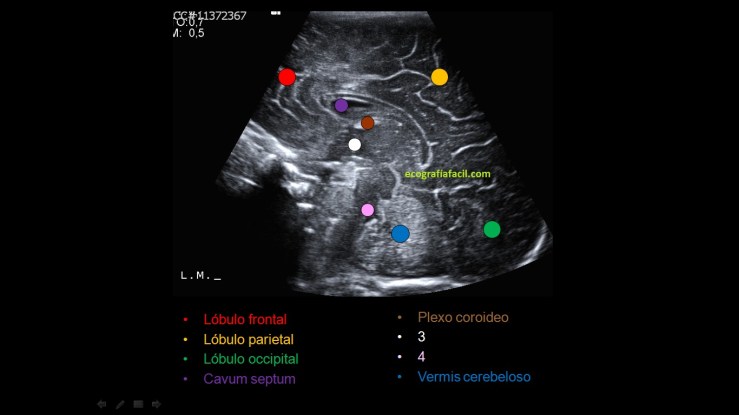

Para explicarte estos cortes necesito una imagen coronal con las angulaciones necesaria para ver la anatomía ecográfica de los sagitales, mira.

Partiendo de un corte sagital central donde a un lado de la pantalla veremos la región frontal y al otro la región occipital, nos angularemos de derecha a izquierda de la cabeza recorriendo toda la cabeza en sagital y si el estudio resulta normal, realizaremos esto resumidamente:

- LÓBULO FRONTAL, LÓBULO PARIETAL, LÓBULO OCCIPITAL, CUERPO CALLOSO, CAVUM SEPTI, PLEXO COROIDEO, TERCER Y CUARTO VENTRÍCULO, SURCO DEL CÍNGULO

To explain these cuts I need a coronal image with the necessary angulations to see the ultrasound anatomy of the sagittals, look.

Starting from a central sagittal section where on one side of the screen we will see the frontal region and on the other the occipital region, we will angle from right to left of the head through the whole head in sagittal and if the study is normal, we will do this briefly:

FRONTAL LOBE, PARIETAL LOBE, OCCIPITAL LOBE, CALLY BODY, CAVUM SEPTI, CHOROID PLEXUS, THIRD AND FOURTH VENTRICLE, SURFACE OF THE CELL